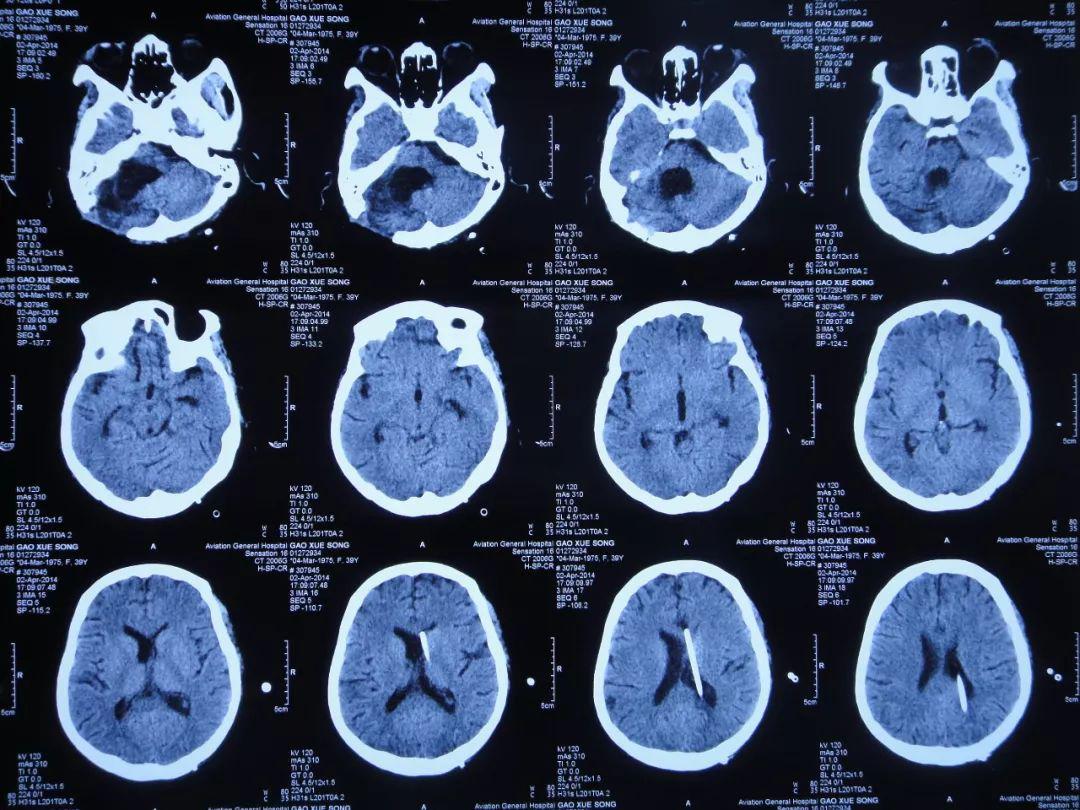

听神经瘤切除术后28天即2013年12月12日,查头颅CT示仍有一侧脑室扩张(图-7)。

图-7:2013年12月12日头颅CT

听神经瘤切除术后42天即2013年12月26日,查头颅CT(图-8)后持续交替给予腰大池引流、腰穿治疗并联合鞘内注射。

图-8:2013年12月26日头颅CT